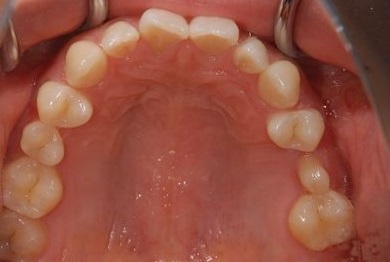

| 性別/年齢 | 女性 / 28歳 | ||||||||||||||||||||||||||||||||

| 主訴 | 下前歯の色が気になるので、ホワイトニングかセラミック治療できれいにしたい。(下前歯2本は乳歯でした) | ||||||||||||||||||||||||||||||||

| 治療方針 | 下顎前歯、乳歯を抜歯し、セラミック治療にて審美的回復を行う。 | ||||||||||||||||||||||||||||||||

| 治療内容 | エンプレスジルコニアフレームオールセラミッククラウンブリッジ4本 | ||||||||||||||||||||||||||||||||